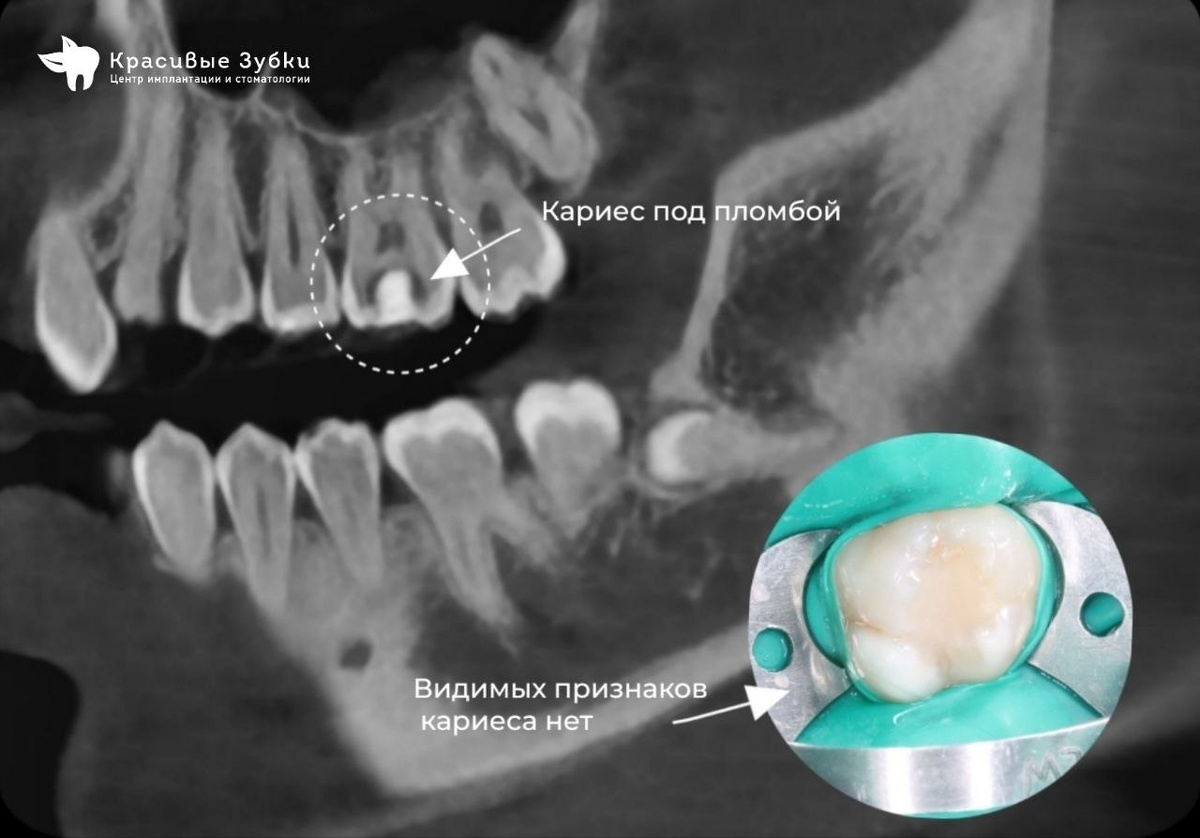

Сделали КТ— на снимке зуба №16 под пломбой обнаружено потемнение, типичное для кариеса.

На снимке КТ обнаружен кариес под пломбой.

• Осмотр: видимых кариозных дефектов не обнаружено. Однако при перкуссии зуб № 16 (верхний правый шестой) возникла лёгкая чувствительность.